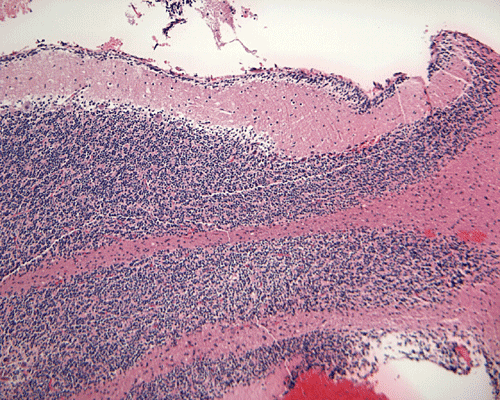

The patient was admitted to our hospital because of a large cerebellar mass that was diagnosed in an outside institution. A surgery was performed. The followings are the representative photos of this mass.

Panel A was a cytologic preparation (squash preparation) and Panel B was the frozen section obtained on intraoperative consultation respectively. Panel C, D, and E were permanent sections obtained from representative areas. Panel F, G and H were cerebellar tissue that was included in the specimen.